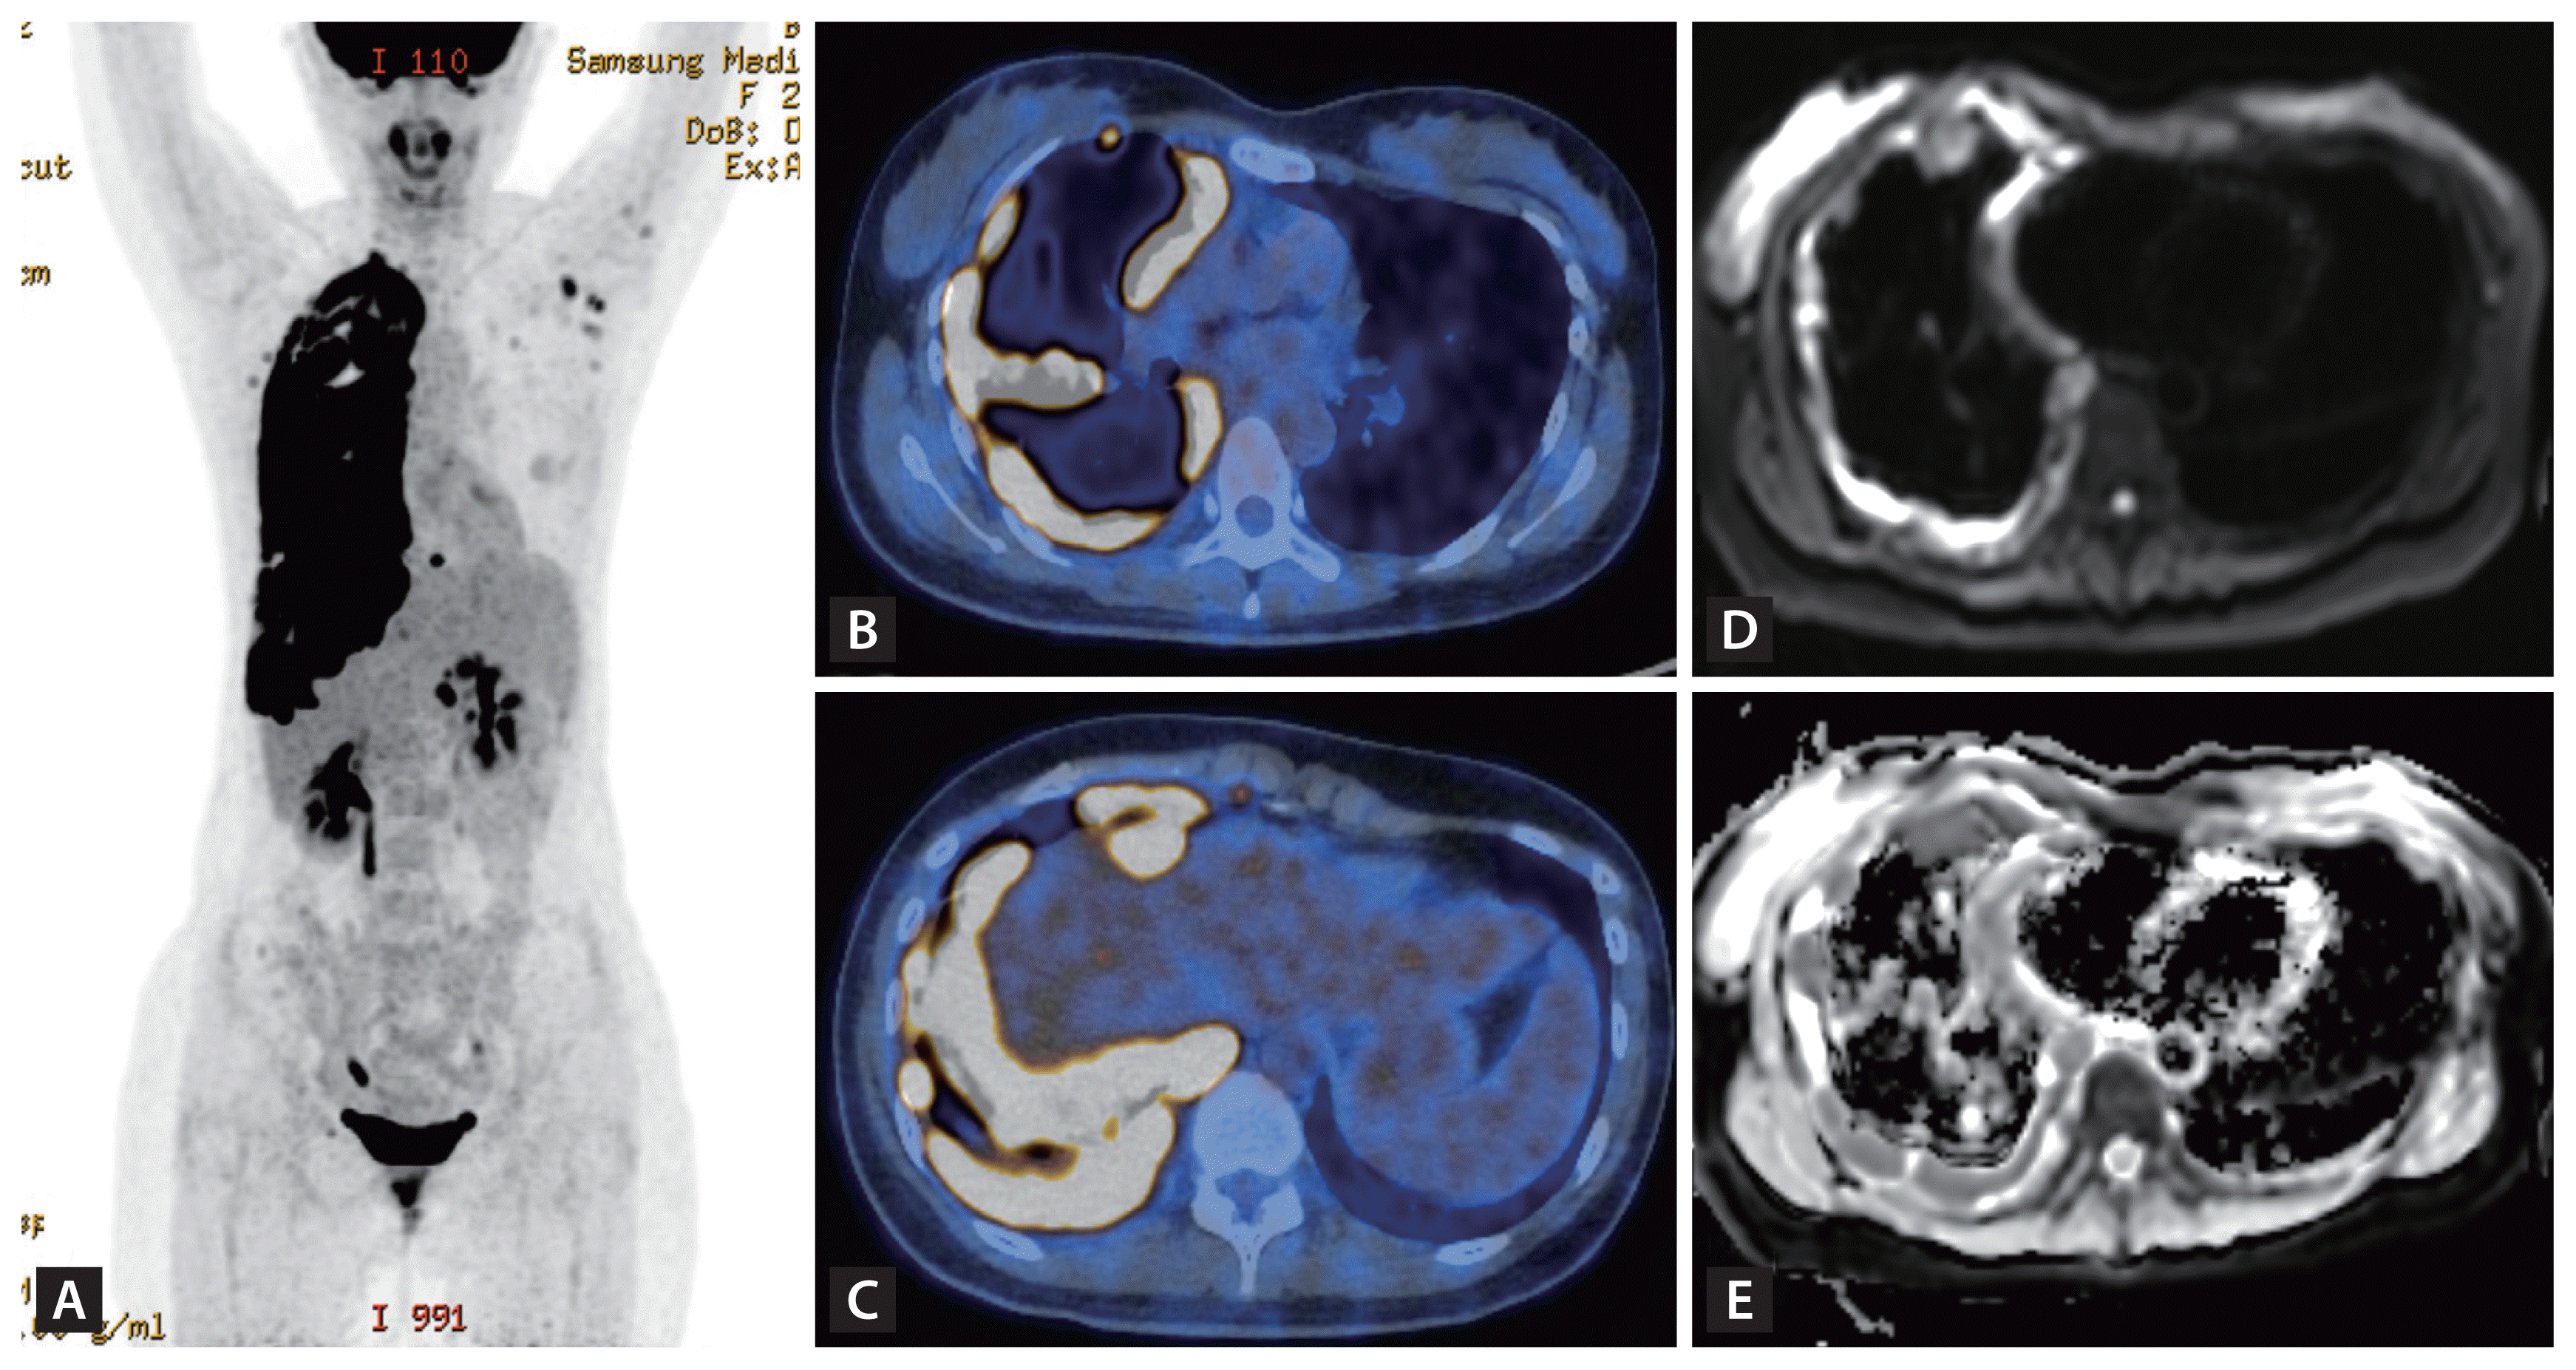

A 26-year-old woman presented to our hospital f or radiologically abnormal pleural lesions at a health check-up. She was asymptomatic with normal laboratory findings. A chest X-ray showed diffuse nodular pleural thickening in the right hemithorax (Fig. 1A). On computed tomography (CT), the extensive pleural thickening involved interlobar fissures and the diaphragmatic pleura, combined with multiple lymphadenopathies in the mediastinum and the anterior diaphragmatic area (Fig. 1B and 1C). These lesions had increased 18F-fluorodeoxyglucose (FDG) uptake on positron emission tomography-computed tomography (PET-CT) (Fig. 2A–2C), suggesting pleural malignancy such as mesothelioma. Chest magnetic resonance imaging (MRI) with enhancement revealed that the pleural lesions showed moderate enhancement after contrast infusion and diffusion restriction on diffusion-weighted images (Fig. 2D and 2E). For a definite diagnosis, video-assisted thoracoscopic pleural biopsy was done. The lesion had chronic granulomatous inflammation with multi-nucleated giant cells with a negative PCR result for Mycobacterium tuberculosis/ non-tuberculous mycobacterium and a few acid-fast bacilli in Ziehl-Neelsen stain. Finally, M. tuberculosis was cultured in bronchial specimens.

Figure 1

Chest X-ray and computed tomography (CT) images on admission (A, B, C). Chest X-ray (A) showed diffuse nodular pleural thickening in the right hemithorax with decreased volume of the right lung. Axial (B) and coronal (C) images of chest CT with enhancement show circumferential nodular pleural thickening in the right hemithorax, involving interlobar fissures and the diaphragmatic pleura.